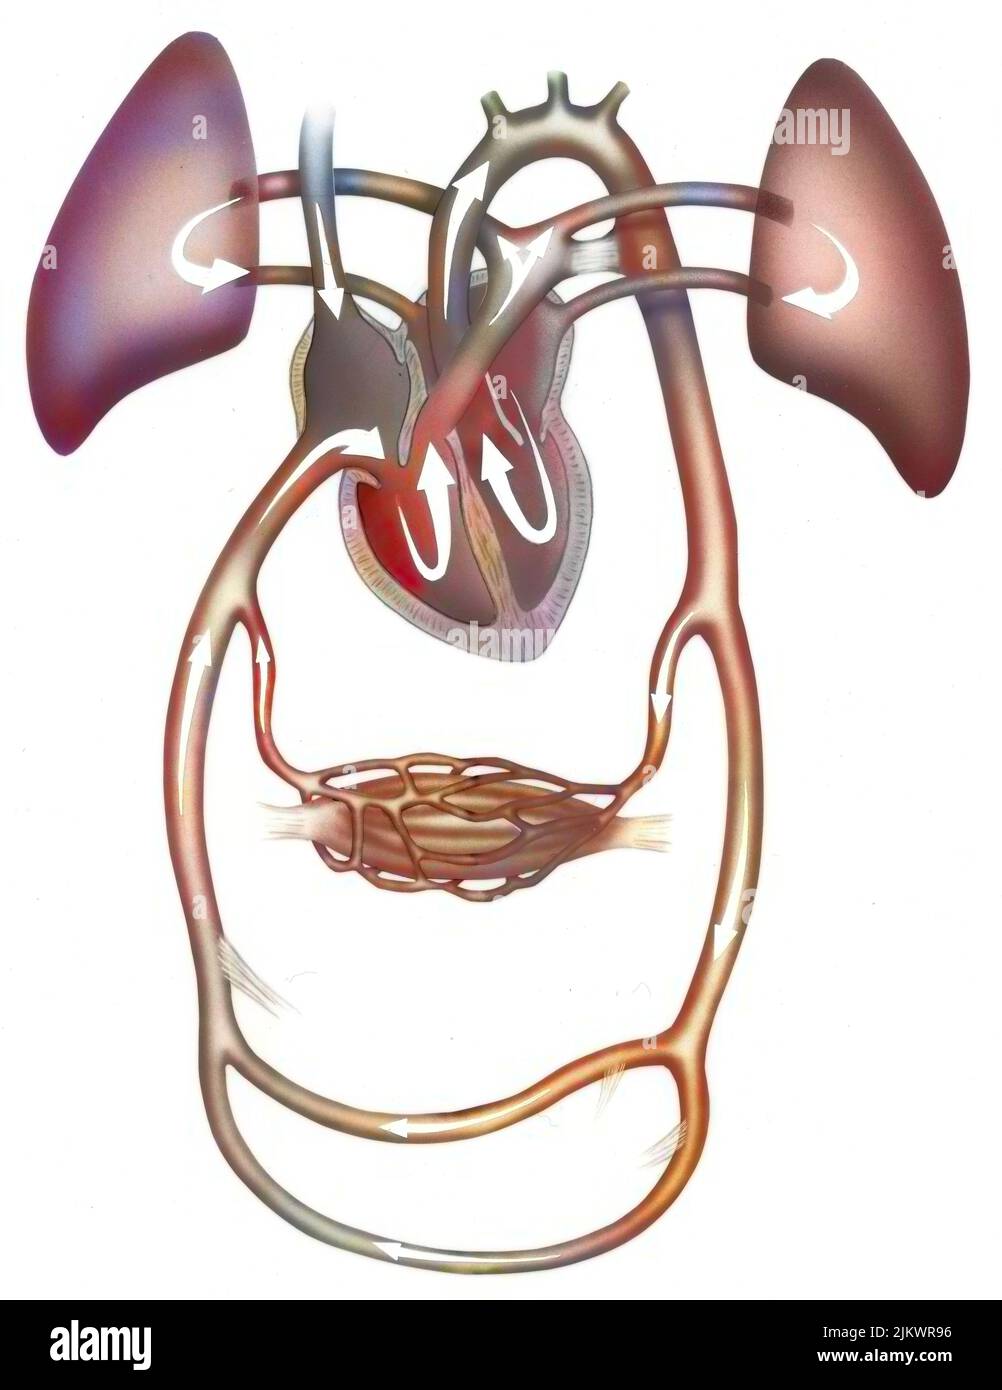

RF2JKWR54–Vaisseau sanguin contenant des globules rouges, des globules blancs, des plaquettes et du plasma.